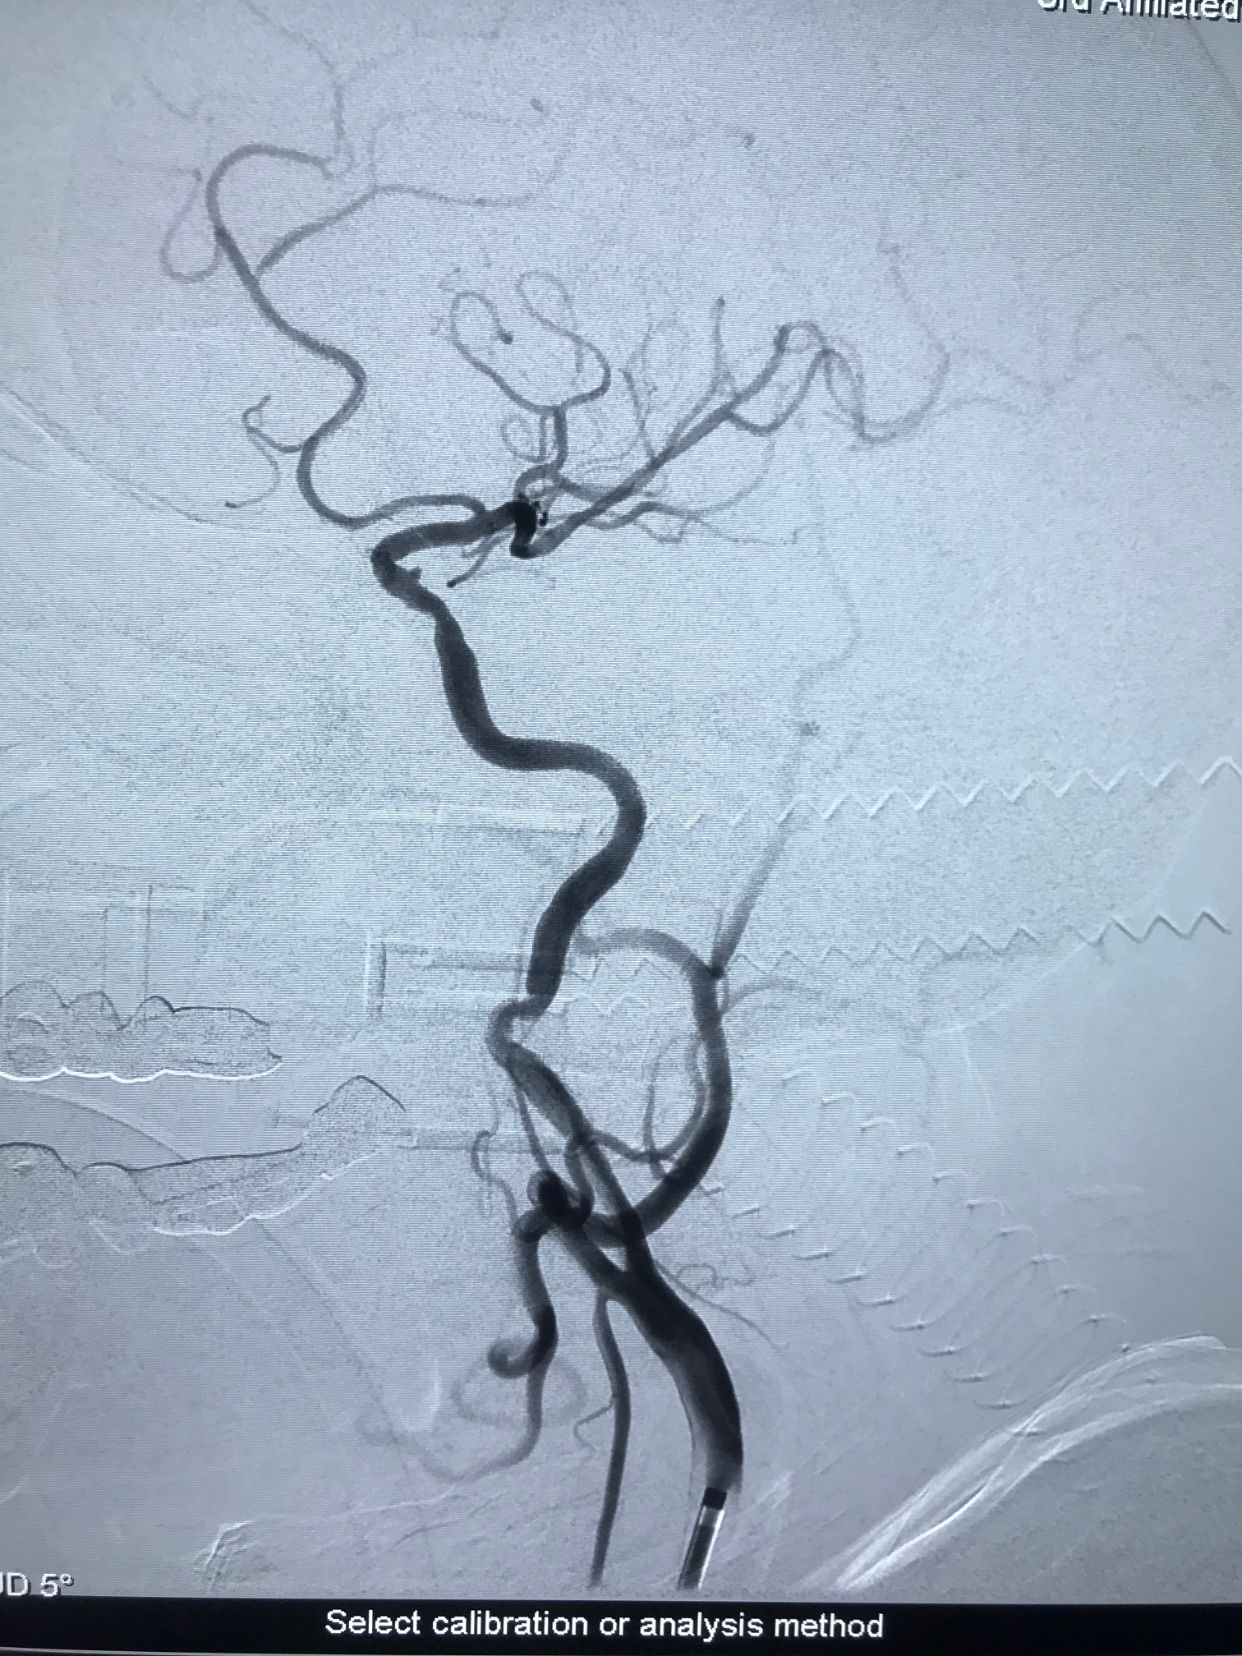

入院后先静脉溶栓,溶栓期间症状加重,右侧肌力持续下降,逐渐出现意识障碍!急诊造影显示左侧颈内动脉开口重度狭窄基础上急性闭塞!

微导丝轻松通过闭塞段,小球囊预扩!

上保护伞!